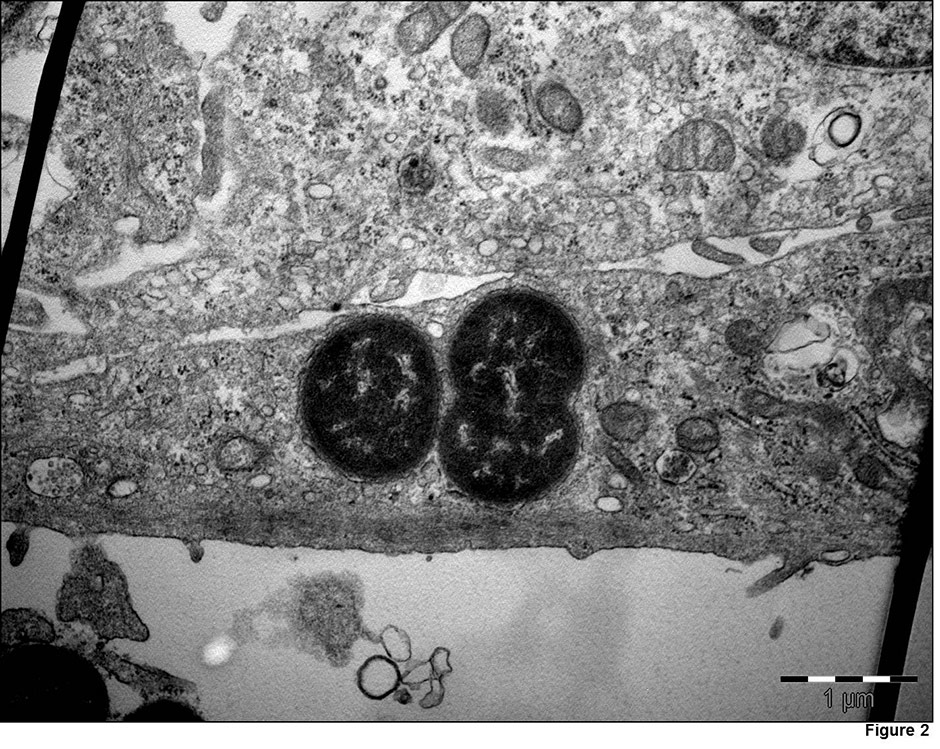

Figure 2

Transmission electron micrographs, demonstrating M. catarrhalis(strain 287) invasion in Detroit 526 pharyngeal cells.

Invasion of human respiratory epithelial cells has been observed mainly in vitro [68, 69]. Invasion is regulated by the expression of LOS, UspA1 [68] and probably other outer membrane components. Slevogt et al. first described the capacity of M. catarrhalis to invade respiratory tract epithelial cells in vitro [69], and Heiniger et al. demonstrated its capacity to invade sub-epithelial pharyngeal lymphoid tissue in vivo [70]. It seems that invasion allows M. catarrhalis to escape killing by the host immune-system and extracellular antibiotics. The relevance and mechanisms of M. catarrhalisinvasion are incompletely understood, and further studies are warranted (fig. 2).